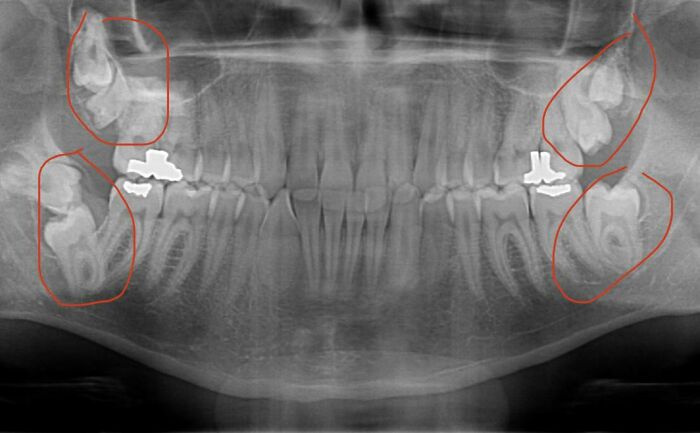

Me extrajeron unas muelas del juicio ganchudas. El cirujano dijo que este era uno de los 10 peores casos que había tenido en sus 30 años de experiencia. Este fue el único que salió entero.